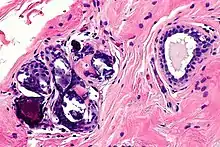

Benign calcification in breast, at high magnification

In most cases, calcification and cysts are the biggest threat of breast augmentation surgery. Fat stem cells failed to pick up a new blood supply will die and be removed from the body by immune cells. However, when this clearing process miss removing dead cells the cluster will lead to calcification and cysts formation. These are visible on the breast as lump sometimes and are more dangerous when these un-picked up dead cells are detected as cancer cells which disturbs accurate diagnosis of breast cancer. The calcified tissue will be diagnosed as a 'benign' cancer and not cause any harm. However, if the tissue is severely damaged the entire breast needs to be removed. Once a patient is diagnosed with calcification of breast implant, regular mammograms should be done to monitor the possible cancer development.[16]